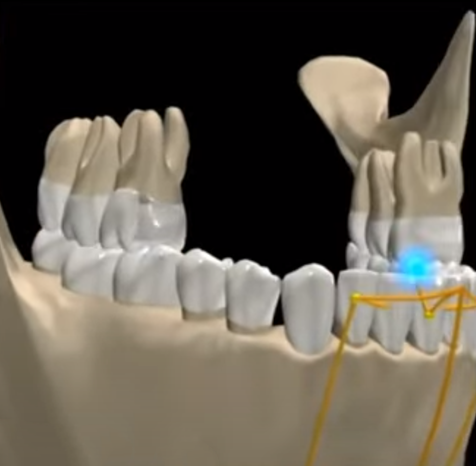

COMiP braces and invisible braces have the same origin. As for the Tooth positioner invented by Keslin in 1942, it was initially used as a maintainer after the correction, Because the Tooth positioner has the ability to position the corrected teeth, adjust the angle and obtain more occlusal contact, Therefore, it can help with tooth movement and correct minor dental differences. Subsequently, multiple sets were used to incrementally move teeth, and this feature was developed into Tooth positioner orthodontic.

The traditional tooth positioner is made in the same way as dentures. According to the upper and lower bite records, the upper and lower articulators are used to make braces that the upper and lower parts can bite together.

In the 1960s, vacuum thermoplastic materials appeared to make maintainers. This method was simpler and more convenient than the Tooth positioner used before. It did not require an articulator and was manufactured directly on the plaster model. The method of using vacuum thermoplastic materials to make retainers is still in use today.

In 1970, Ponitz developed early translucent correction based on the concept of Tooth positioner orthodontic at that time. Until Hermit Beauty uses digital design of teeth and 3D printing to produce invisible braces, Slight increments and multiple pieces allow for more space movement, fulfilling Keskin’s wish back then. However, this correction method lacks the interactive movement of the upper and lower bites. Therefore, it can effectively align the teeth, but it cannot accurately align the upper and lower bites.

The technology of the 21st century, the application of oral scanning and orthodontic software, has given the traditional Tooth positioner orthodontic a glimmer of hope. Nowadays, the teeth can be arranged neatly in the same way as invisible braces, and then based on the characteristics of the Tooth positioner, braces with gnathological positioner can be made based on the teeth arranged in a type of occlusal position.

The advantage of this designed Tooth positioner silicone braces is that, like invisible braces, the teeth are moved through the power of vertical occlusion, and the teeth can be arranged according to the ideal occlusal relationship.

COMiP uses the characteristics of Tooth positioner to establish the occlusion relationship of the Maximal Intercuspal Position (MIP) of Class I occlusion. This position is also called Central Occlusion (CO). During the mixed dentition period, it guides the tooth alignment of the upper and lower jaws. The method of positioning is used to guide the growth and arrange the teeth. Finally, the teeth are replaced and the teeth are arranged neatly.

COMiP two-stage early correction system. Our design has patents in many countries around the world. It is also the only system in the world that has four corrections. It is used in early correction. During the correction process, bone, teeth, muscle function and respiratory tract correction are gradually completed, providing a comprehensive solution. Problems with growing children. How to complete correction in two stages